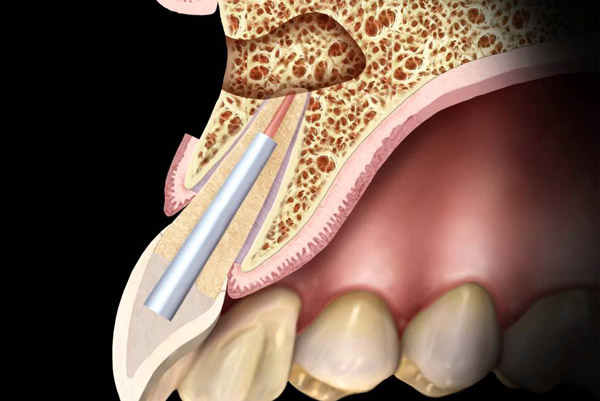

tooth During the procedure, your dentist or endodontist cuts through your gum and pushes the gum tissue aside in order to reach the root. Usually just a few millimeters of the root are removed, as is any infected tissue surrounding the root.

tooth After the root tip is removed, the root canal inside the tooth is cleaned and sealed with a small filling to prevent future infection. Your dentist or endodontist may then take another X-ray to make sure your tooth and jaw look good and that there are no spaces where a new infection could take hold.

tooth The tissue will then be sutured (stitched), so your gum can heal and grow back in place. Your jawbone will also eventually heal around the filling at the end of the root. You shouldn’t feel much, if any, pain or discomfort during the procedure.